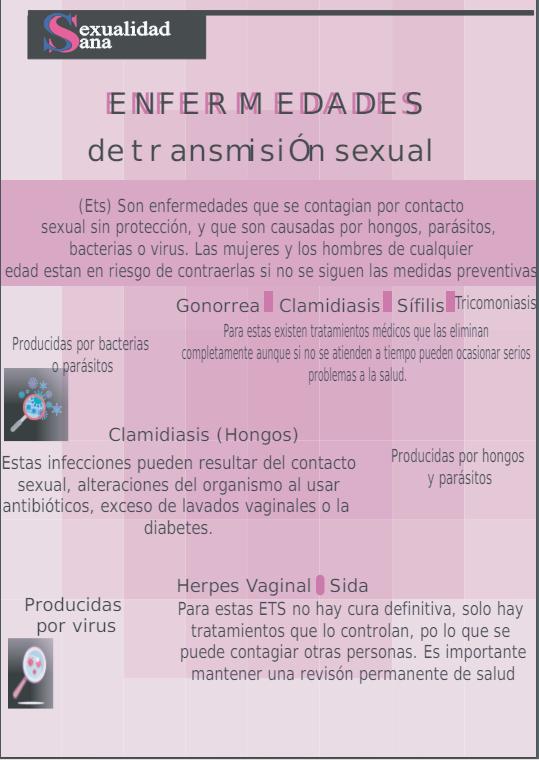

5. INFECCIONES DE TRANSMISIÓN SEXUAL

5.1. Tipos de ITS

Chancroide.- Es una infección de transmisión sexual caracterizada por una úlcera dolorosa en el sitio de inoculación, por lo general en los genitales externos

Chlamydia tracomatis.- Los síntomas son similares a los de la gonorrea, causada por una bacteria que afecta a la uretra en los hombres, y al cuello uterino en las mujeres; transmitida por contacto con mucosas de la vagina, boca, ojos, uretra o recto.

Gonorrea.- Es causadas por un microbio llamado Neisseria gonorrhoeae, que vive en las áreas más templadas y húmedas del organismo, principalmente en la uretra y cuello uterino.

Sífilis.- Se trata de una entidad que ha sufrido un marcadísimo descenso en las últimas décadas, pero los últimos años a retomando influencia debido a la infección del VIH. Es más frecuente en el sexo masculino.

La sífilis se transmite durante el sexo oral, vaginal y anal, durante el embarazo y por transfusiones sanguíneas. En mujeres embarazadas puede provocar la muerte del feto o del recién nacido o transmitirse al neonato

El uso correcto y sistemático de preservativos durante las relaciones sexuales puede prevenir la enfermedad.

Infección por VIH/SIDA.- Es una enfermedad infecciosa que afecta al sistema inmunológico humano, encargado de proteger el organismo de las agresiones externas. Al agente causante del SIDA se le denomina Virus de la Inmunodeficiencia Humana (VIH).

El VIH se transmite principalmente a través de contacto sexual sin protección, compartir agujas contaminadas, transfusiones de sangre no seguras o de madre a hijo durante el embarazo, el parto o la lactancia materna.

Aunque no existe una cura para el VIH, los avances médicos han llevado al desarrollo de terapias antirretrovirales que pueden ayudar a controlar la infección y permitir que las personas infectadas vivan vidas más largas y saludables.

La prevención sigue siendo fundamental en la lucha contra el VIH/SIDA, incluyendo el uso de condones durante las relaciones sexuales, la realización de pruebas de detección regulares, el acceso a la educación sobre salud sexual y reproductiva.

El acceso a servicios médicos y tratamientos adecuados. La reducción del estigma y la discriminación hacia las personas que viven con VIH también es crucial para garantizar que reciban el apoyo y la atención que necesitan.